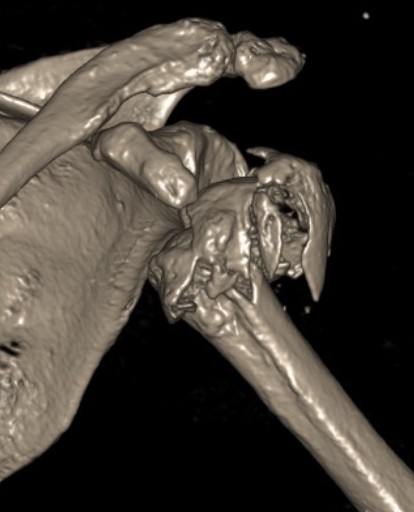

Severe comminuted proximal humerus fractures

100% displaced / off ended

Fracture - dislocations

Unreconstructable fracture - 4 part, comminuted, head spltting fracture